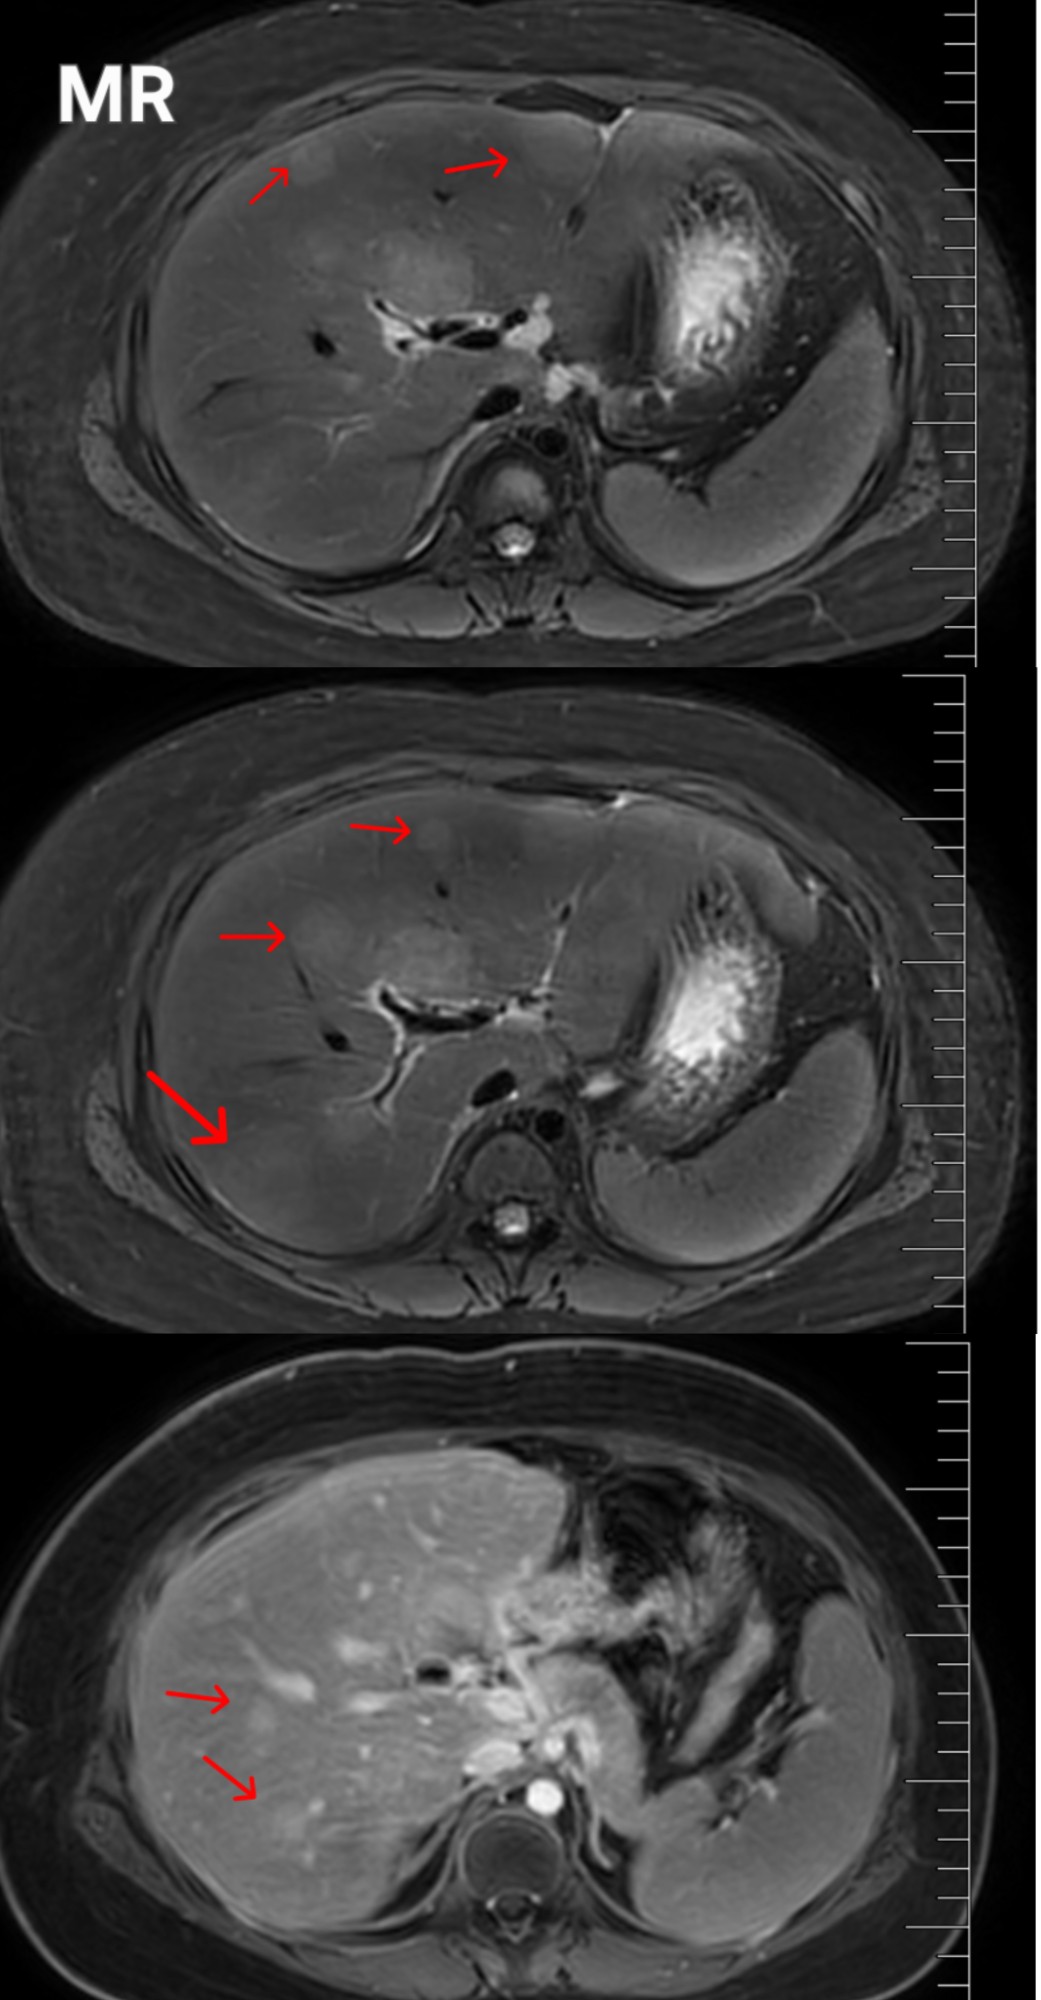

可检查结果带来了新的疑问:腹部超声提示 “肝内多发低回声区,脓肿可能”,而进一步完善增强 MR则提示 “肝脏多发异常信号,考虑转移瘤”。对于有神经母细胞瘤病史的小喜而言,肝内占位的性质直接关系到后续治疗方向与预后,家长的神情瞬间变得凝重,心理承受着巨大压力。

控制住急性感染后,明确肝内占位的性质成为后续治疗的关键。为避免单一学科的局限,实现最精准的诊疗,郝薇迅速启动MDT诊疗模式,紧急报请医务处组织影像科、感染性疾病科、肿瘤科、肝胆外科四位一体的专家团队进行会诊。各科专家立足专业视角,梳理病情难点,综合分析影像学特征、临床表现及治疗反应,深入分析,打破学科壁垒,凝聚集体智慧。最终达成共识:肝内占位考虑局灶性结节增生可能性最大,暂不考虑转移瘤及肝脓肿。这一结果让大家紧绷的神经得到缓解,但仍需后续随访复查。基于MDT讨论结果,专家团队为小喜制定了精准的个体化治疗方案,并建立长期随访机制,为宝贝保驾护航。